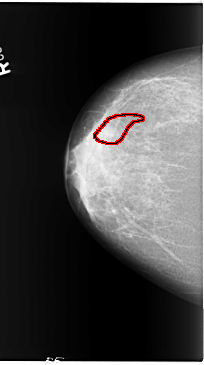

B_3095_1.RIGHT_CC

RIGHT_CC LINES 5840 PIXELS_PER_LINE 3256 BITS_PER_PIXEL 12 RESOLUTION 50 OVERLAY

FILE: B_3095_1.RIGHT_CC.OVERLAY

TOTAL_ABNORMALITIES 1

ABNORMALITY 1

LESION_TYPE CALCIFICATION TYPE PLEOMORPHIC DISTRIBUTION SEGMENTAL

ASSESSMENT 4

SUBTLETY 3

PATHOLOGY BENIGN

TOTAL_OUTLINES 1

BOUNDARY